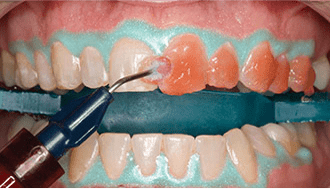

オフィスホワイトニング施術方法

1

1. お口の状態と、歯の色調を確認

2

2. ホワイトニング材を塗布する準備をします。歯肉保護などを行います。

3

3. ホワイトニングジェルの塗布を行います。

4

4. 歯の色調の変化を歯科医師と確認します。